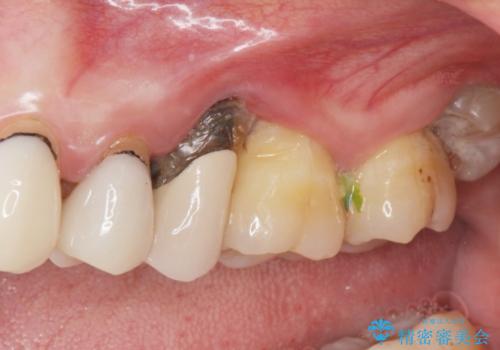

- 黒く変色し、ぐらぐらする歯の改善を求めて来院されました。

X線、歯周組織検査の結果、残すことができない歯周病の進行が左上小臼歯に認められました。

抜歯後は、インプラントではなくブリッジを選択されました。